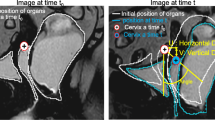

Figure 7 shows an example of single-slice and multi-slice sequence images from a symptomatic patient with POP.

38-year old primiparous woman with symptomatic pelvic organ prolapse in involving all three compartments and a POP-Q score of III. Sagittal single-slice (a, c) and multi-slice (b, d) MR images at rest (a, b) and maximum straining (c, d) are shown. The bladder (white arrow), cervix (black arrow) and anorectal junction (white arrowhead) are annotated. At rest, the bladder point was 1.6 cm and 1.6 cm, the cervix point was 4.1 cm and 3.7 cm, and the anorectal junction was 1.4 cm and 1.0 cm above the PICS line in the single-slice and multi-slice sequences, respectively. During maximum straining, the bladder point was 4.1 cm and 3.4 cm below, the cervix point was 0.2 cm and 0.0 cm above, and the anorectal junction was 3.1 cm and 3.1 cm below the PICS line in the single-slice and multi-slice sequence, respectively. Differences between single and multi-slice sequences were small (0.1–0.4 cm at rest and 0.0–0.7 cm at straining) and there was no difference in the POP grading between the single-slice and multi-slice sequence (grade 2 descent of the anterior compartment, and grade 1 descent of the posterior compartment)